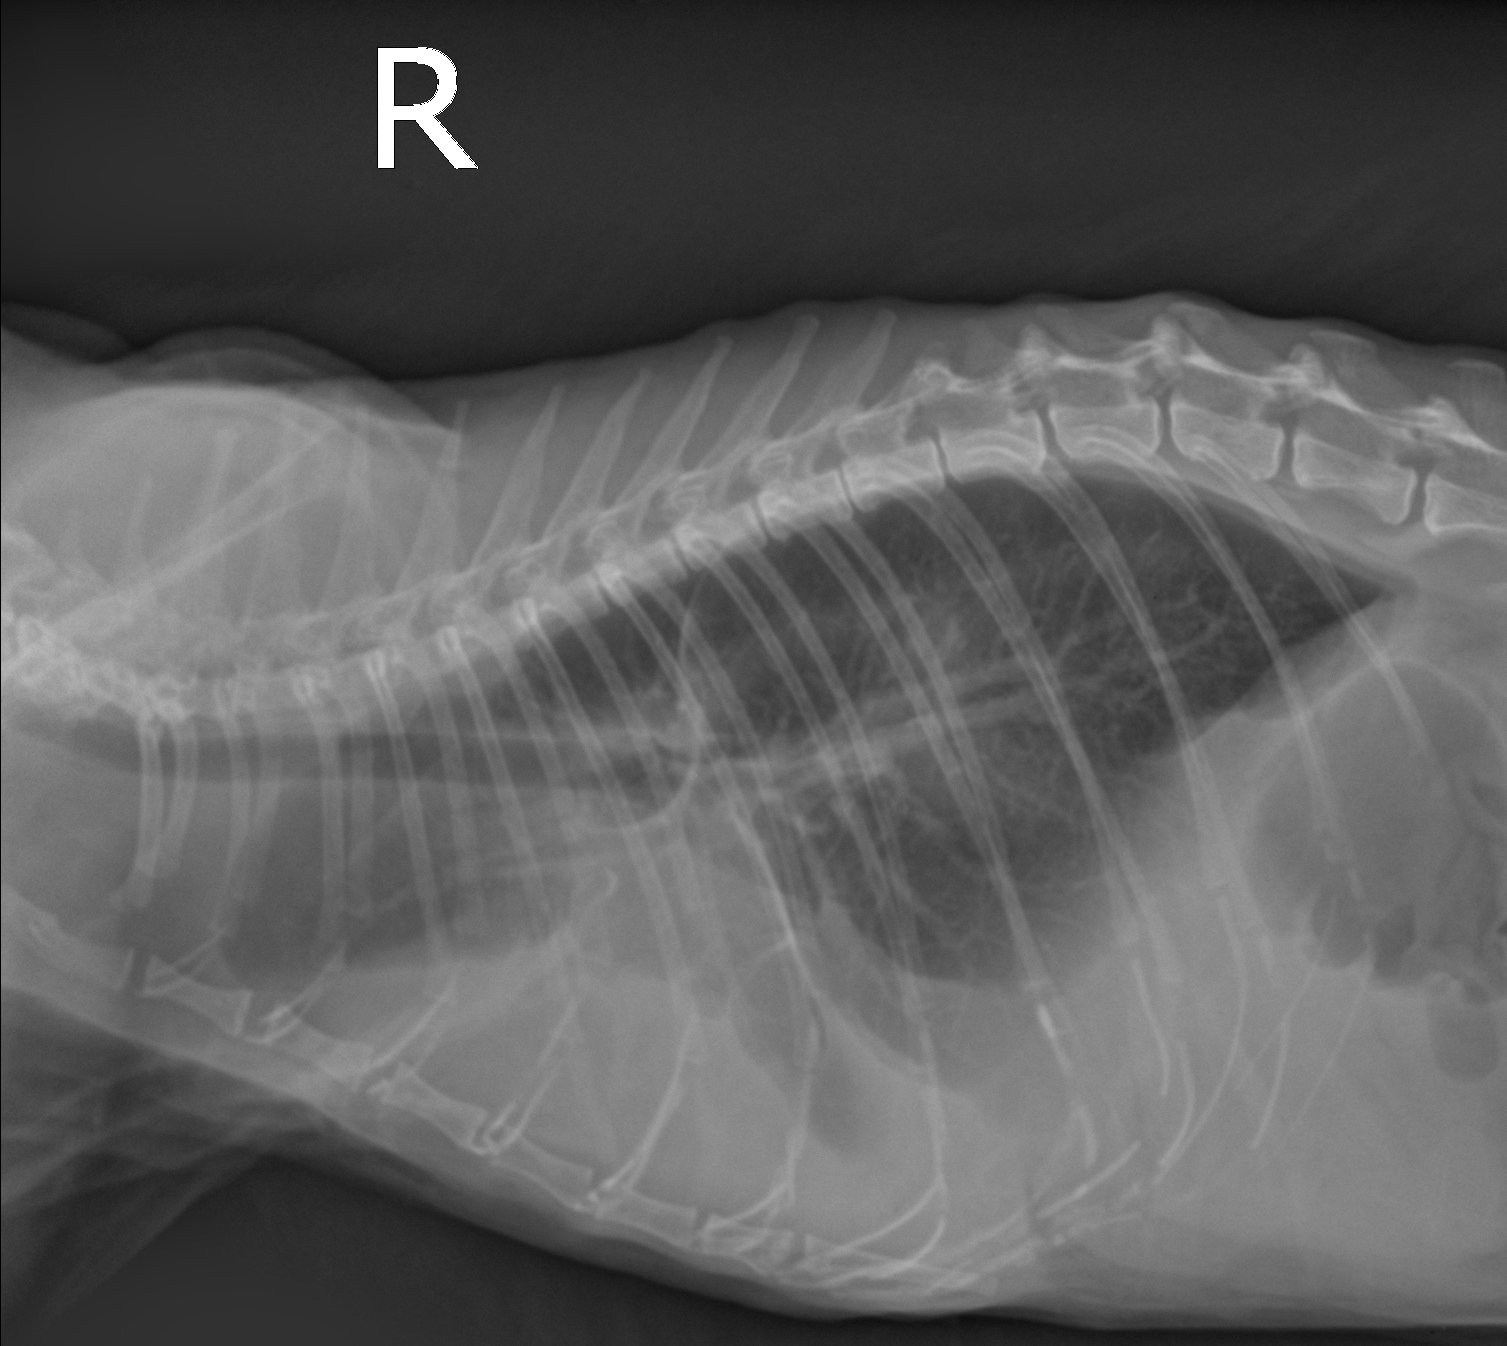

Рентген как метод диагностики легочных гельминтов у кошек: что нужно знать владельцам

Легочные гельминты у кошек – это опасные паразиты, которые могут вызвать серьезные заболевания дыхательной системы. Одним из эффективных методов диагностики является рентгеновское исследование, позволяющее выявить их наличие в легких. В этой статье мы расскажем, как этот метод помогает в диагностике и что нужно знать владельцам домашних питомцев.

Рентген может помочь не только обнаружить гельминтов, но и выявить возможные осложнения в легких.

Для точной диагностики сочетайте рентгеновские снимки с анализами кала на наличие яиц гельминтов.

Рентгеновское исследование помогает выявить даже скрытые инфекции, которые могут не проявляться на начальных стадиях.

После лечения следует повторно пройти рентген, чтобы убедиться в эффективности терапии.

Дирофилярии (Сердечно-легочные черви)